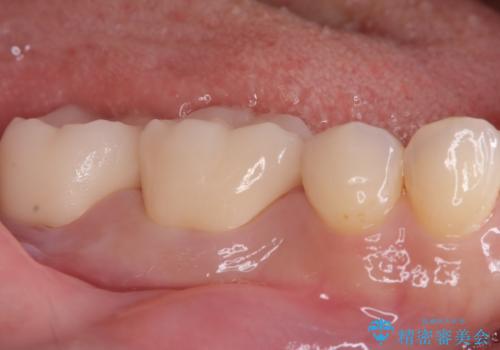

歯の根元の虫歯も精密治療で解決

- 右下6番と7番の奥歯に、歯の根元部分の虫歯(根面カリエス)を認め来院されました。通常の虫歯よりも進行しやすい根面カリエスは、再発リスクを抑えた治療が重要です。患者様のご希望と口腔内の状態を考慮し、虫歯を徹底的に除去し、精密で耐久性の高いセラミッククラウンで修復する治療計画を立案しました。これにより、長期的な再発防止と咬み合わせの機能回復を目指します。

治療ではまず、感染した歯質をマイクロスコープで確認しながら慎重に除去。その後、セラミッククラウンを装着するための歯の形成を行いました。型取りから患者様の歯の形や色に合わせたオーダーメイドのセラミッククラウンを作製。セラミックは、プラークが付着しにくく、再治療のリスクを低減する特性があります。最終的に、精度の高いクラウンを装着し、咬み合わせを細かく調整しました。これにより、根面カリエスが再発しにくい環境を整え、快適に食事ができる奥歯を取り戻していただけました。